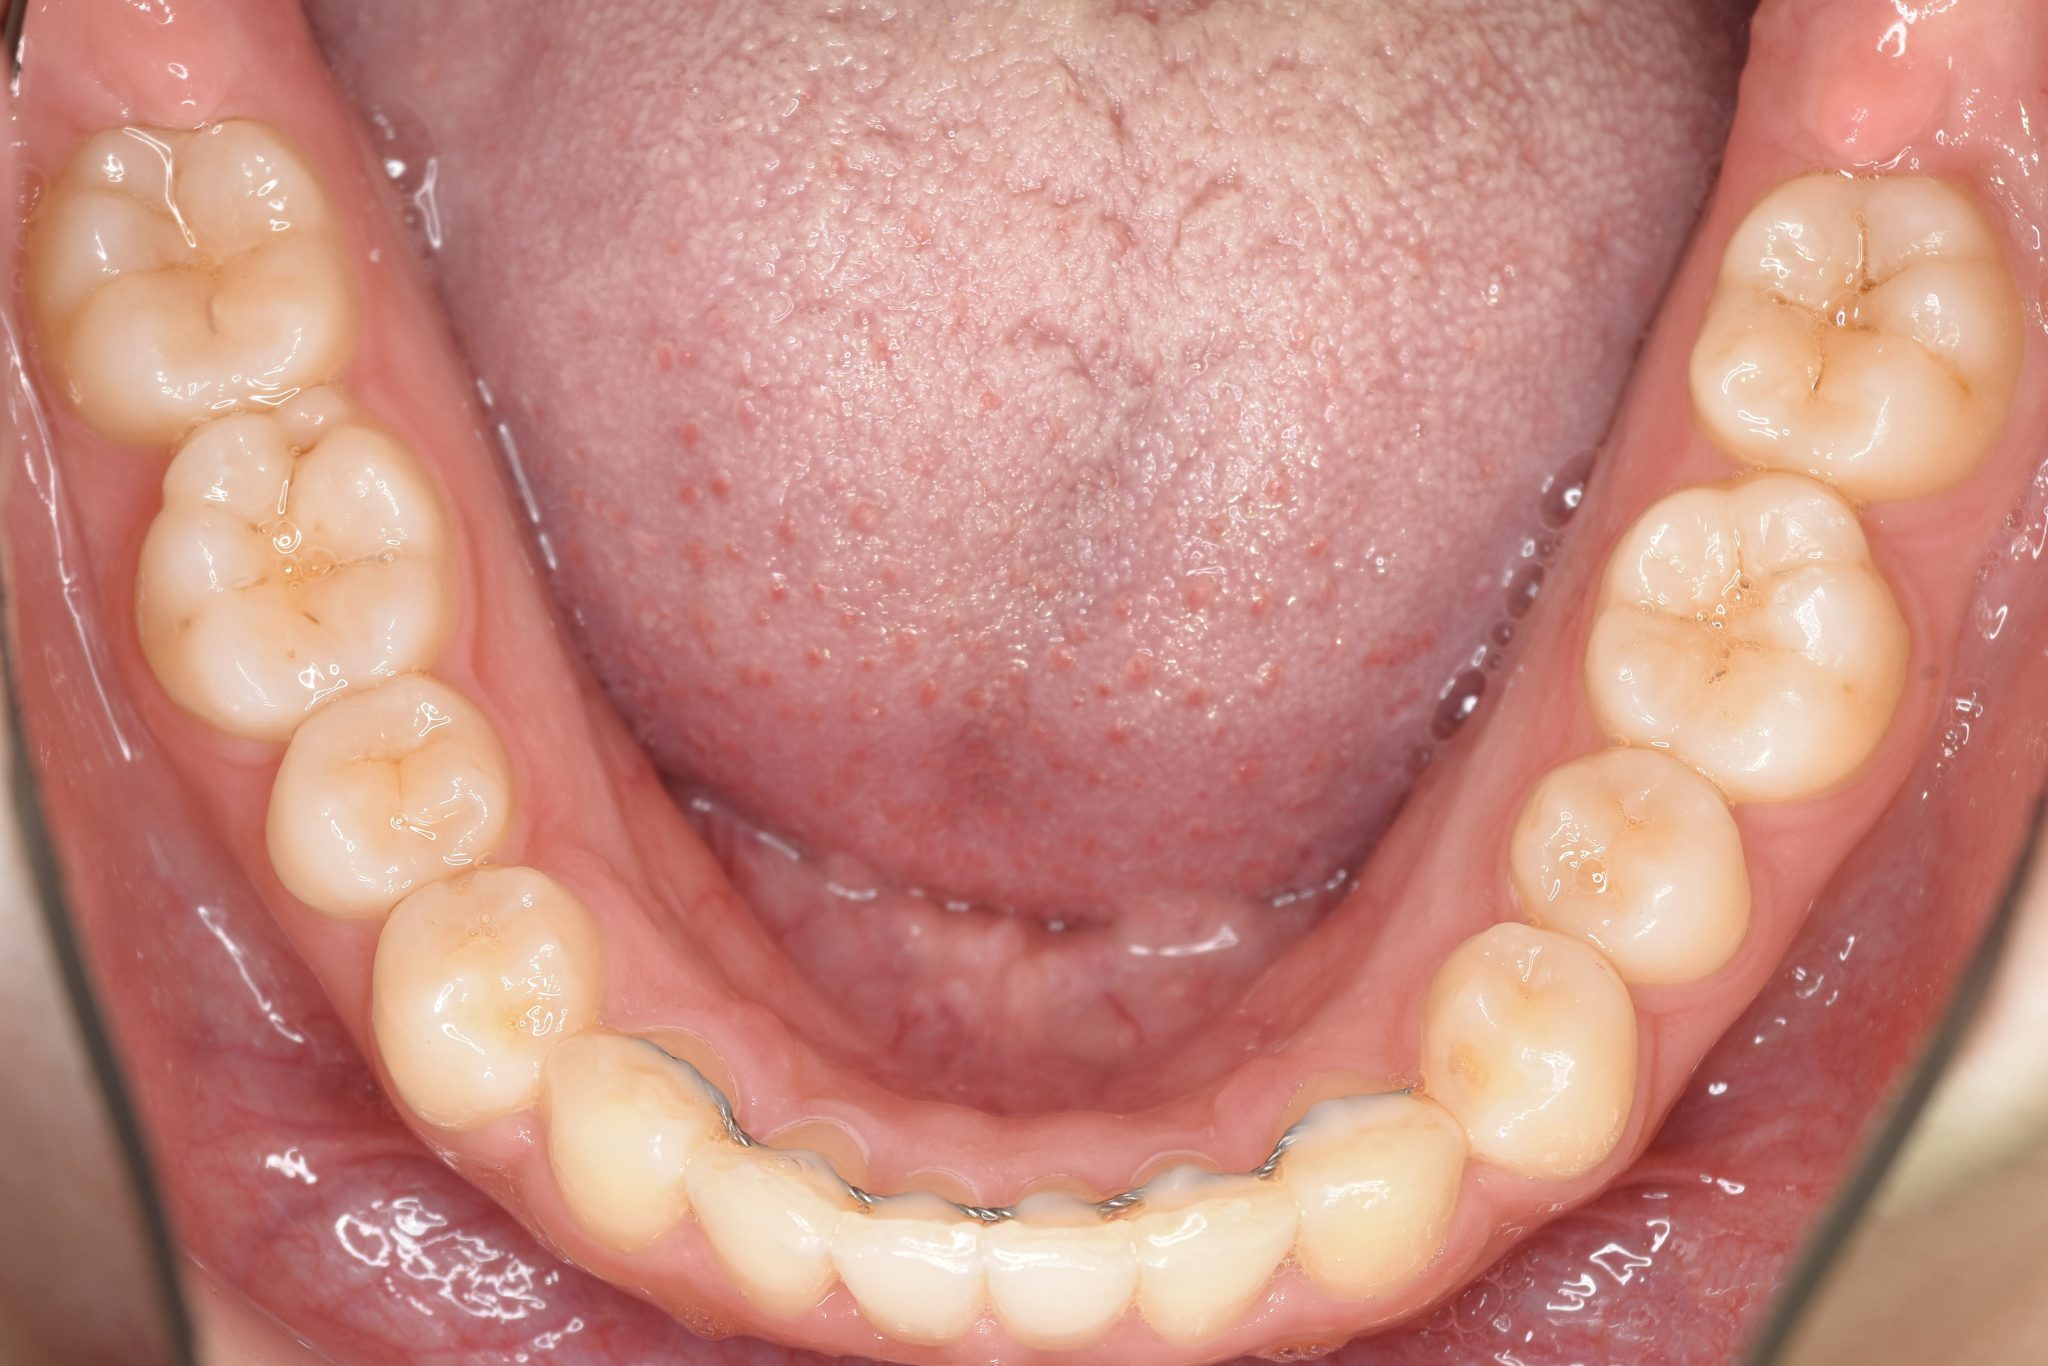

ビフォー

インビザライン矯正治療|症例_315

アフター

主訴 食べ物を前歯で噛み切れない|上顎の右側の歯が重なっている|下の歯がガタガタ

施術内容 MSEと下顎リンガルアーチを用いて上下顎骨を拡大した。

その後アライナー型矯正装置(インビザライン)を用いて非抜歯で歯牙を配列した。

口元の突出感、鼻閉症状、鼾は改善された。

治癒期間 1年6ヶ月間